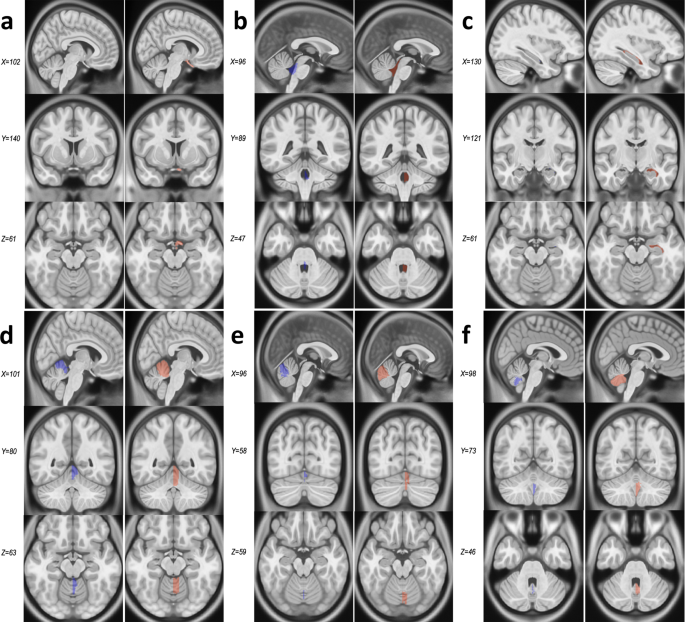

When comparing CerebrA to original labels from Mindboggle-101 (Fig. 2) registered to ICBM152, the average Dice Kappa value was κ = 0.73 ± 0.18 (Table 1). The structures with relatively lower Dice Kappa (κ < 0.6) corresponded to the structures that needed the most correction such as the optic chiasm, inferior lateral ventricles, fourth ventricle and cerebellar vermis. The optic chiasm label was barely found in the original Mindboggle-101 registered to ICBM152 and most of it was misaligned with regards to the actual structure. To ensure that this inaccuracy was not caused by the nonlinear registration process, we further inspected the original Mindboggle-101 template and label atlas and found similar issues. For CerebrA, the optic chiasm label was redefined trying to achieve continuity amongst optic chiasma itself and optic tracts (Fig. 3, panel a). Then, the inferior lateral ventricles and fourth ventricle boundaries were improved using a threshold to differentiate CSF from parenchyma (Fig. 3, panels b and c). And finally, cerebellar vermis labels were redefined for right and left side (Fig. 3, panels d–f).

Comparison between Mindboggle-101 and CerebrA for structures with Dice Kappa < 0.6. Panel a. Optic chiasm. Panel b. Fourth ventricle. Panel c. Inferior lateral ventricle. Panels d–f. Cerebellar vermis lobules. For each structure, the column on the left (blue) represents the original labels from Mindboggle-101, warped onto the ICBM152 symmetric template, and the right column (pink) represents CerebrA’s right sided corresponding labels, on the same template.